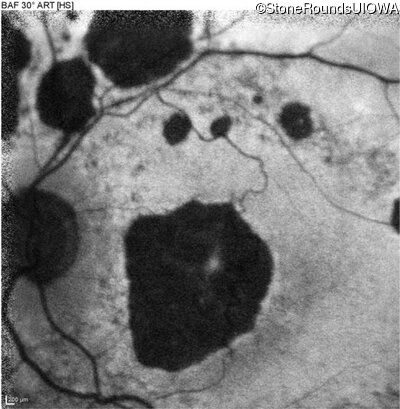

Blue Autofluorescence - Right - 20/125 -2

Exemplar

Blue Autofluorescence - Left - 20/125 +2